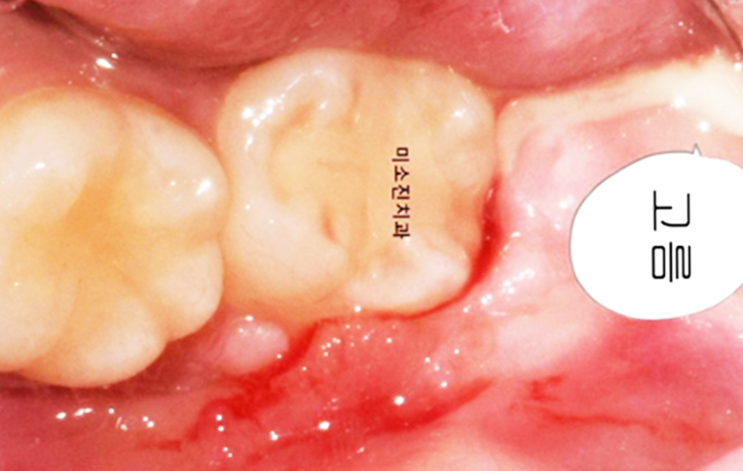

어금니 뒤 잇몸 통증 약 2가지

어금니 뒤 안쪽 잇몸통증 약 2가지 갑자기 어금니 뒤 잇몸통증이 느껴진다면 다양한 이유가 있을 수 있지만...